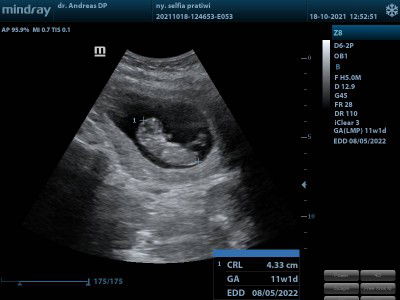

buat periksa ke dokter. karena tanggal 20 harus kontrol calon debay lagi